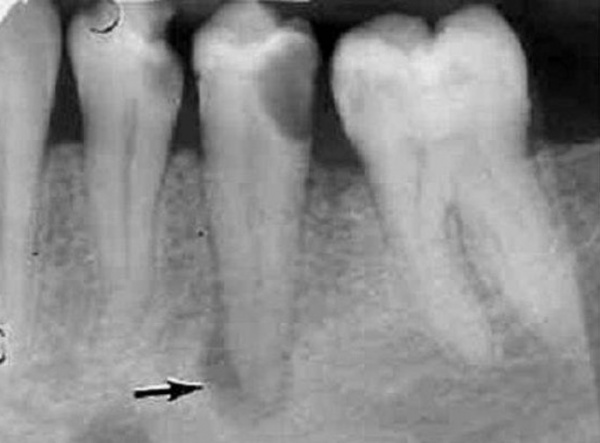

На рентгенограмме нижней челюсти: деструкция костной ткани округлой формы с чёткими ровными контурами, в полость выстоят корни нижних передних зубов (32, 31 и 41).

Если периапикальный абсцесс сформировался при обострении хронического фиброзного периодонтита, рентгенографически определяют расширение периодонтальной щели в участке верхушечной трети корня. Характерным рентгенологическим признаком хронического гранулематозного периодонтита является участок деструкции костной ткани округлой формы диаметром до 5 мм вокруг верхушки причинного зуба. При образовании периапикального абсцесса на фоне хронического гранулирующего периодонтита на прицельной рентгенограмме выявляют деструктивные изменения в периапикальной зоне с неровными контурами, напоминающими «языки пламени». Может наблюдаться резорбция корней. Периапикальный абсцесс дифференцируют с острым периодонтитом, обострением хронического периодонтита, пародонтальным абсцессом, периоститом, остеомиелитом, нагноением радикулярной кисты. Клинический осмотр проводят стоматолог-терапевт, стоматолог-хирург.

- Рентгенография зуба. В случае хронического гранулирующего периодонтита в апикальной области обнаруживается участок разрежения костной ткани с нечеткими границами размерами от 1 до 8 мм. Хронический гранулематозный периодонтит характеризуется ясно очерченными округлыми контурами области разрушения костной структуры вокруг верхушки корня зуба. Хронический фиброзный периодонтит на рентгенограмме проявляет себя расширенным периодонтальным пространством в апикальной области при отсутствии резорбции костной стенки альвеолы.